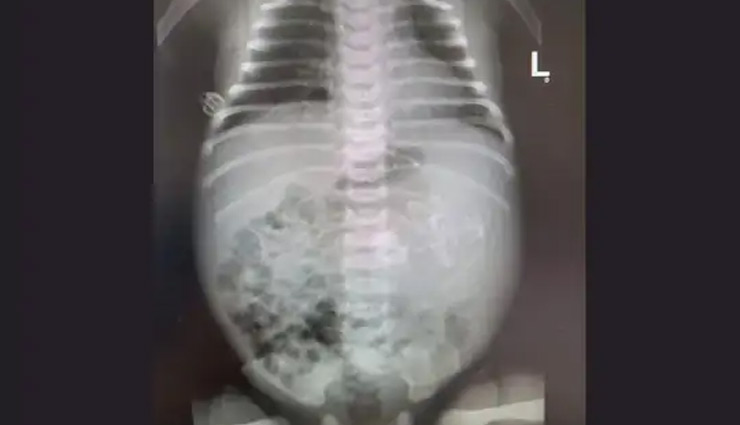

बंदर को निगलने के बाद अजगर की जान पर बन आई, वन कर्मियों ने बचाया